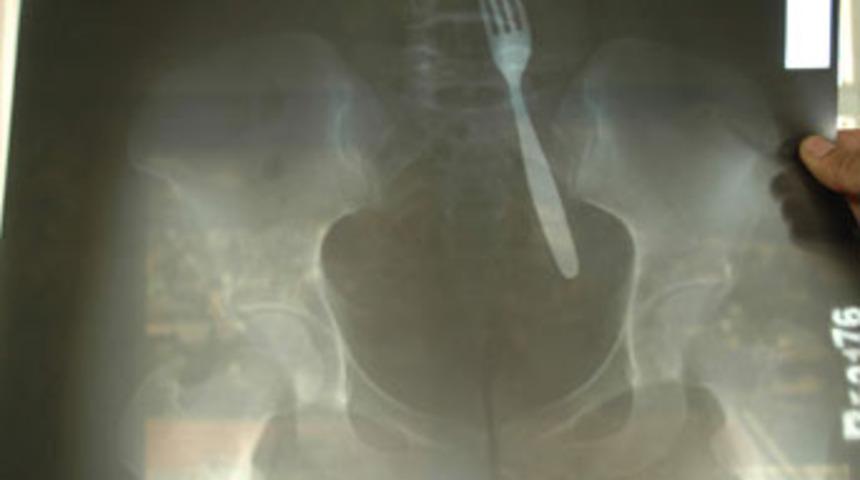

Kahramanmaraş'ın Afşin ilçesinde bir genç kız, karın ağrısı şikayetiyle gittiği hastanede, midesinde çatal olduğunu öğrenince şok oldu. Genç kızın çatalı küçük yaşta yuttuğu sanılırken, çatal başarılı bir ameliyatla çıkarıldı.

Afşin'de yaşayan 24 yaşındaki Ayfer Karakaya, karın ağrısı şikayetiyle hastaneye başvurdu. Acil serviste yapılan ilk kontrollerin ardından filmi çekilen Karakaya'nın midesinde çatal olduğu ortaya çıktı. Midesinde çatal olduğunu öğrenen genç kız, nasıl olduğuna bir türlü anlam veremezken, doktoru bir aYıllarca midesinde çatalla yaşadı 1n önce ameliyat olması gerektiğini söyledi. Bunun üzerine yapılan operasyonla, Karakaya'nın midesindeki çatal çıkarıldı.

Ameliyatı gerçekleştiren Dr. Ali Özpolat, genç kızın midesindeki çatalı görünce kendisinin de şaşırdığını ifade ederek, "Bu, tıpta ender vakalardan biri diye düşünüyorum. Hastamız çatalı ne zaman yuttuğunu hatırlamıyor. Muhtemelen çok küçük yaşlarda olabileceğini tahmin ediyoruz" dedi. Çatalı ince bağırsaktan çıkardıklarını anlatan Özbolat, ameliyatın çok başarılı geçtiğini ve hastanın sağlık durumunun iyi olduğunu ifade etti.

Ayfer Karakaya ise, çatalın nasıl midesine gittiğini bilmediğini belirterek, "Gerçekten şok oldum. Psikolojim bozuldu. Nasıl olduğunu hatırlamıyorum bile" diye konuştu.

Zaman zaman karın ağrısı çektiğini anlatan Karakaya, "Şiddetli karın ağrısı ile hastaneye müracaat ettim. Doktorlar ilk anda önemli bir şey olmadığını söylediler. Ağrı kesici iğne yaptıktan sonra filme gönderdiler. Filmden sonra midemde çatal olduğu ortaya çıktı. Resmen şok oldum. Doktorum küçük yaşta çatalı yutmuş olabileceğimi söyledi. Ben hatırlamıyorum" ifadelerini kullandı.